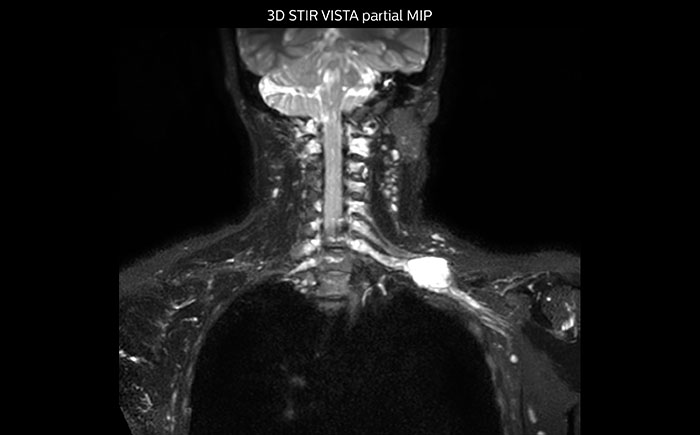

MR neurography of nerve sheath lesion

This patient is a 43-year-old female with a left supraclavicular nerve sheath tumor. The lesion is well visualized on the STIR VISTA images and on the MR neurography using DWIBS. The exam was performed on Prodiva 1.5T.

Acq voxel size 1.2 x 1.3 x 2.4 mm, Recon voxel size 0.7 x 0.7 x 1.2 mm, dS SENSE factor 2, scan time 5:46 min.